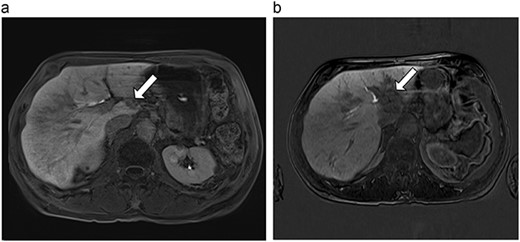

(a) Pre-ablation MRI demonstrating 14 mm lesion in caudate lobe of liver. (b) Post-ablation MRI (23 days postoperatively) demonstrating 23.8 mm complete ablation of caudate lesion.

| 4 (6a,b) | 51, M | Colon adenocarcinoma | 6 cycles FOLFOX | 4 | Laparoscopic microwave ablation | 14 | 23.8 | 9.8 | 13 | Yes |